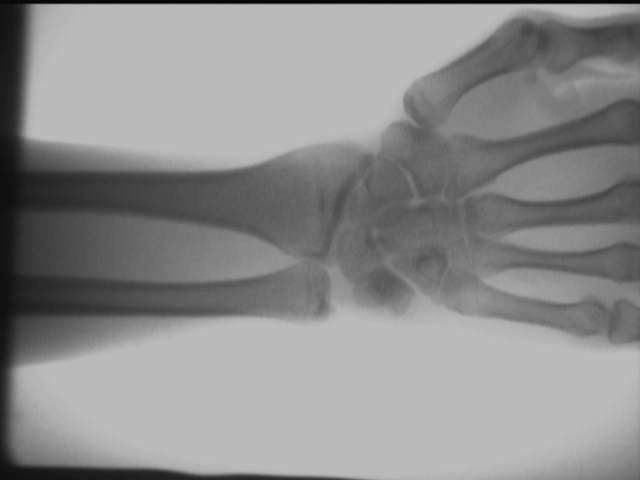

Käden nilkkanivelvaikutus

Yllä olevat testitulokset saadaan paikan päällä AS-C200:llakannettava röntgenlaite